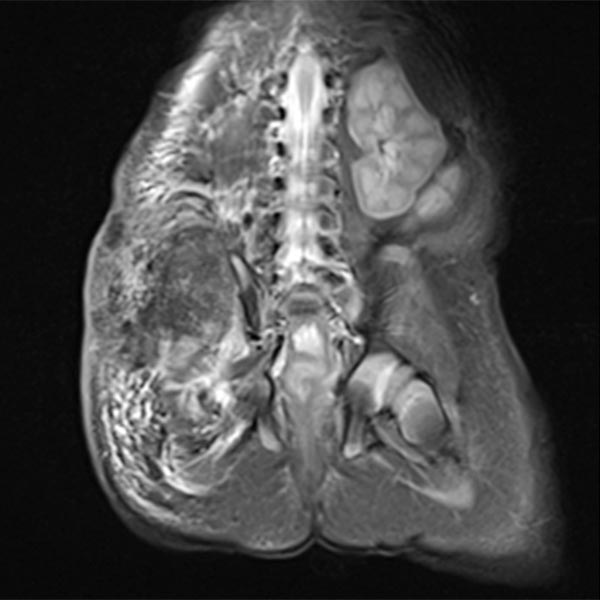

Native T1-weighted MRI shows the tumor to be hypointense. The tumor has blurred margins. The surrounding adipose tissue is saturated with lymphedema.

In corresponding T2-weighted, fat-saturated MRI, the tumor shows hypointense parts (hemorrhages), but also hyperintense parts and is overall very inhomogeneous and blurred. The surrounding fat tissue is saturated with lymphedema.

This surrounding subcutaneous lymphedema (hyperintense in axial T2-weighted, fat-saturated MRI ) is a typical feature of kaposiform hemangioendothelioma and also extends significantly in the surrounding area.